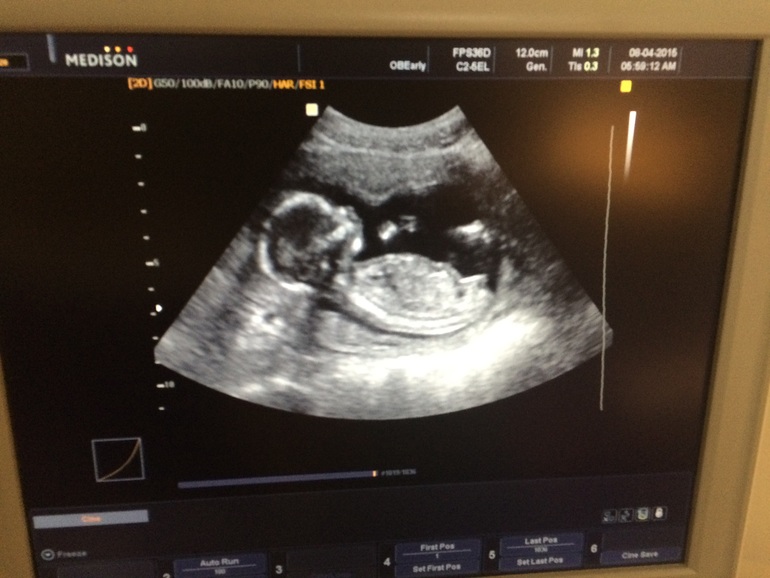

я наблюдаюсь в платной клинике, в ней же записалась на внеплановое узи, предполагая, что за мои деньги любой каприз, но оказалось что узистка позвонила уже моему врачу с вопросом "что это Сергеева на узи записалась, есть волнения какие-то?)))" Короче приходим мы, а она нам - "и что мне писать? Пришли пол посмотреть?)))", я грю да ничего не пишите мы как за обычное узи геникологии оплатим в кассу) она грит "неет, так не получится, ты же наблюдаешься тут, надо в карту заносить". Муж сделал фирменные щенячьи глаза)))) В общем она в итоге махнула рукой и говорит ложись! )))) Ляльке говорит "давай показвай что там у тебя, родители у тебя нетерпеливые"))) ну и короче это ОНА, процентов на 90) узистка за прием ничего не взяла, сказала чтоб мы ее не сдавали и якобы она нас не приняла))

Я б тоже не утерпела))) у меня знакомая одна есть,уже троих родила и пол во время беременности специально просила не говорить — мол,пусть это сюрпризом будет)) не представляю,КАК можно иметь такую выдержку))PS.Такие вы уже большие на узи)))